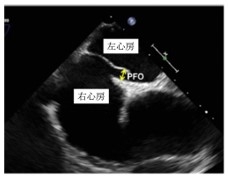

2. 卵円孔開存症の診断

卵円孔開存症は、心エコー検査にて診断されます。

経胸壁心エコーにて、診断ができることもありますが、最終的には経食道心エコーを行うことにより診断がつきます。

卵円孔閉鎖術はカテーテルを用いて左心房→右心房の順にディスクを広げ、卵円孔を閉鎖する治療です。将来的には、留置されたデバイスは内皮化されることが分かっています。

デバイスのサイズはいくつかあり、卵円孔開存症の大きさによって選択されます。麻酔法は全身麻酔と局所麻酔があり、患者さんの状態等によって選択されます。治療時間は1〜2時間で、入院期間は約4日間です。